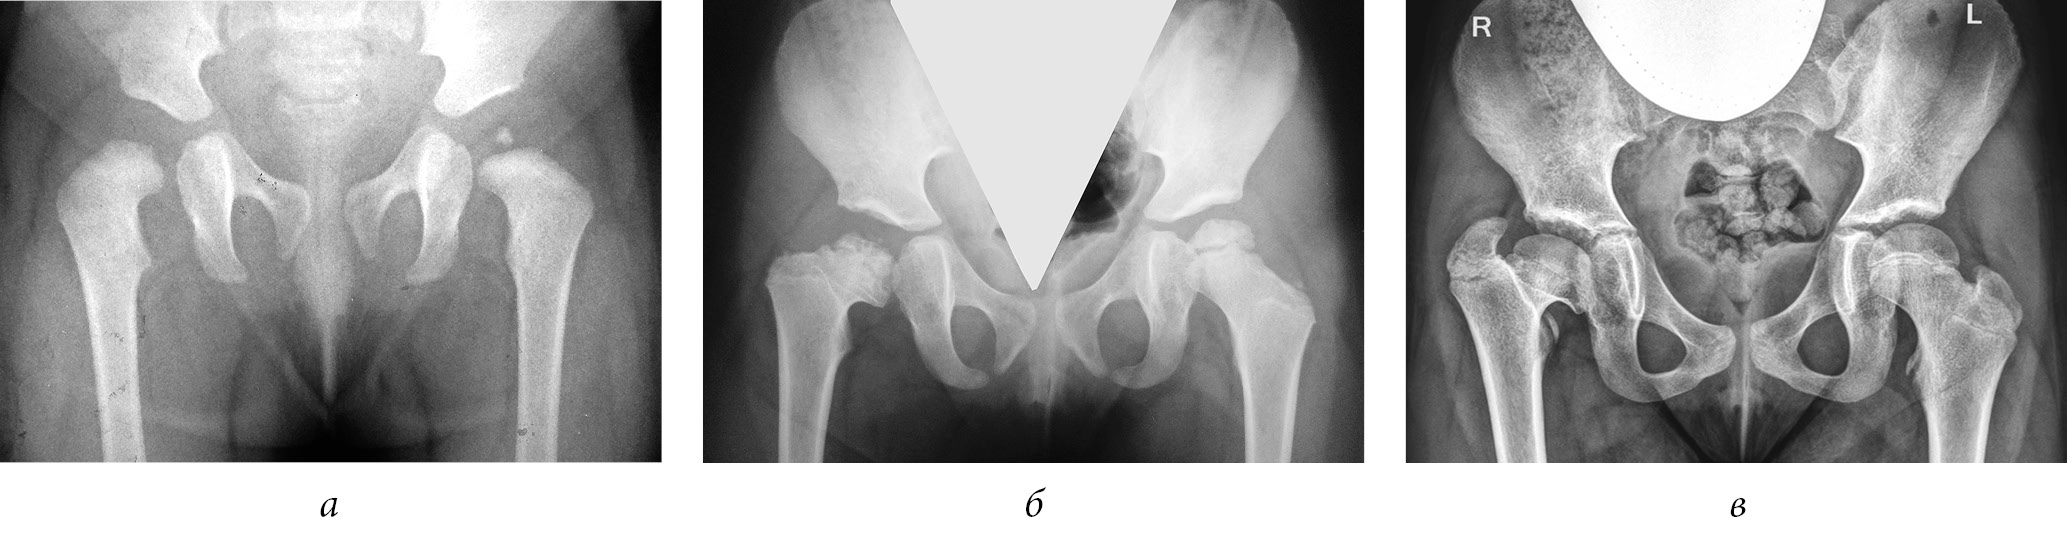

1) последствия ишемического некроза головки бедренной кости как осложнения консервативного лечения при дисплазии тазобедренных суставов и врожденном вывихе бедра —143 (40,9 %) ребенка (рис. 3);

Рис. 3. Рентгенограммы пациентки Ш. Формирование многоплоскостной деформации проксимального отдела бедренной кости с высоким положением большого вертела после перенесенного аваскулярного некроза головки бедренной кости (справа — IV типа, слева — II типа по Kalamchi и MacEwen). В анамнезе — консервативное лечение по поводу врожденного вывиха бедра с двух сторон: а — в возрасте 1 года 2 месяцев; б — в возрасте 3 лет 9 месяцев; в — в возрасте 11 лет

2) последствия гематогенного остеомиелита (септического артрита) — 101 (28,9 %) ребенок. В эту группу также вошли пациенты, перенесшие внутриутробные инфекции и хирургические вмешательства на первом году жизни по поводу врожденных пороков сердца, атрезии пищевода, кишечной непроходимости, трахеопищеводных свищей, осложнившиеся инфекционным поражением тазобедренных суставов (рис. 4);

Рис. 4. Рентгенограммы пациентки Ж., 7 лет. Последствия гематогенного остеомиелита — многоплоскостная деформация проксимального отдела бедренной кости с высоким положением большого вертела слева: а — прямая проекция; б — проекция по Лауэнштейну